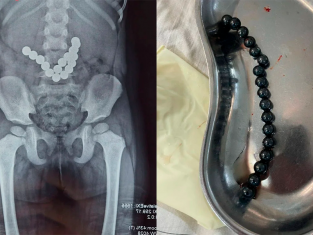

Операция второго шанса: в Ташкенте спасли ребенка после критической ошибки лечения |

Операция второго шанса: в Ташкенте спасли ребенка после критической ошибки лечен